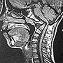

Chiari Malformation:

A brain malformation characterized by a small or misshapen posterior fossa (compartment in the back of the skull), and a protrusion of the structures in the back of the brain(cerebellar tonsils) into the spinal canal. Chiari Malformations were first described in the 1890's by a German pathologist, professor Chiari. He assigned a grade to the malformations: beginning with type one the mildest form through type four the most severe. A colleague, Dr. Arnold, added to the type two description and hence the name "Arnold- Chiari Malformation".

Syringomyelia:

A chronic spinal disorder in which cerebrospinal fluid enters the spinal cord, forming a cavity known as a syrinx. Doctors sometimes use other words such as cyst, hydromyelia, or syringohydromyelia. In most cases syringomyelia(SM) is related to a congenital malformation (Chiari). However, not all patients with Chiari Malformation will develop a syrinx. SM can also occur as a complication of spinal trauma, meningitis, tumor, or arachnoiditis. In these cases a syrinx develops in the section of the spinal cord damaged by these conditions. The symptoms of SM are numerous and a person may have various combinations of symptoms. The common symptoms include: loss of sensitivity, especially to hot and cold, muscle weakness and spasticity, motor impairement, loss of bladder and bowel control. Sensory problems such as numbness, tingling, burning and sweating problems may occur. The majority of patients suffer from headaches and chronic pain.